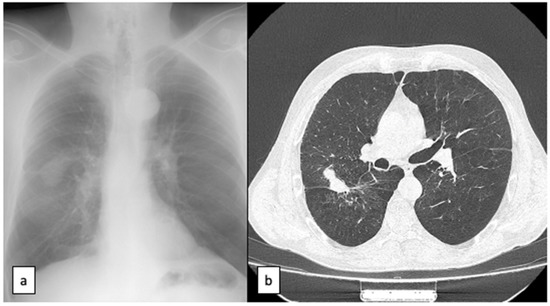

2. Case Report

3.2. Imaging Diagnosis